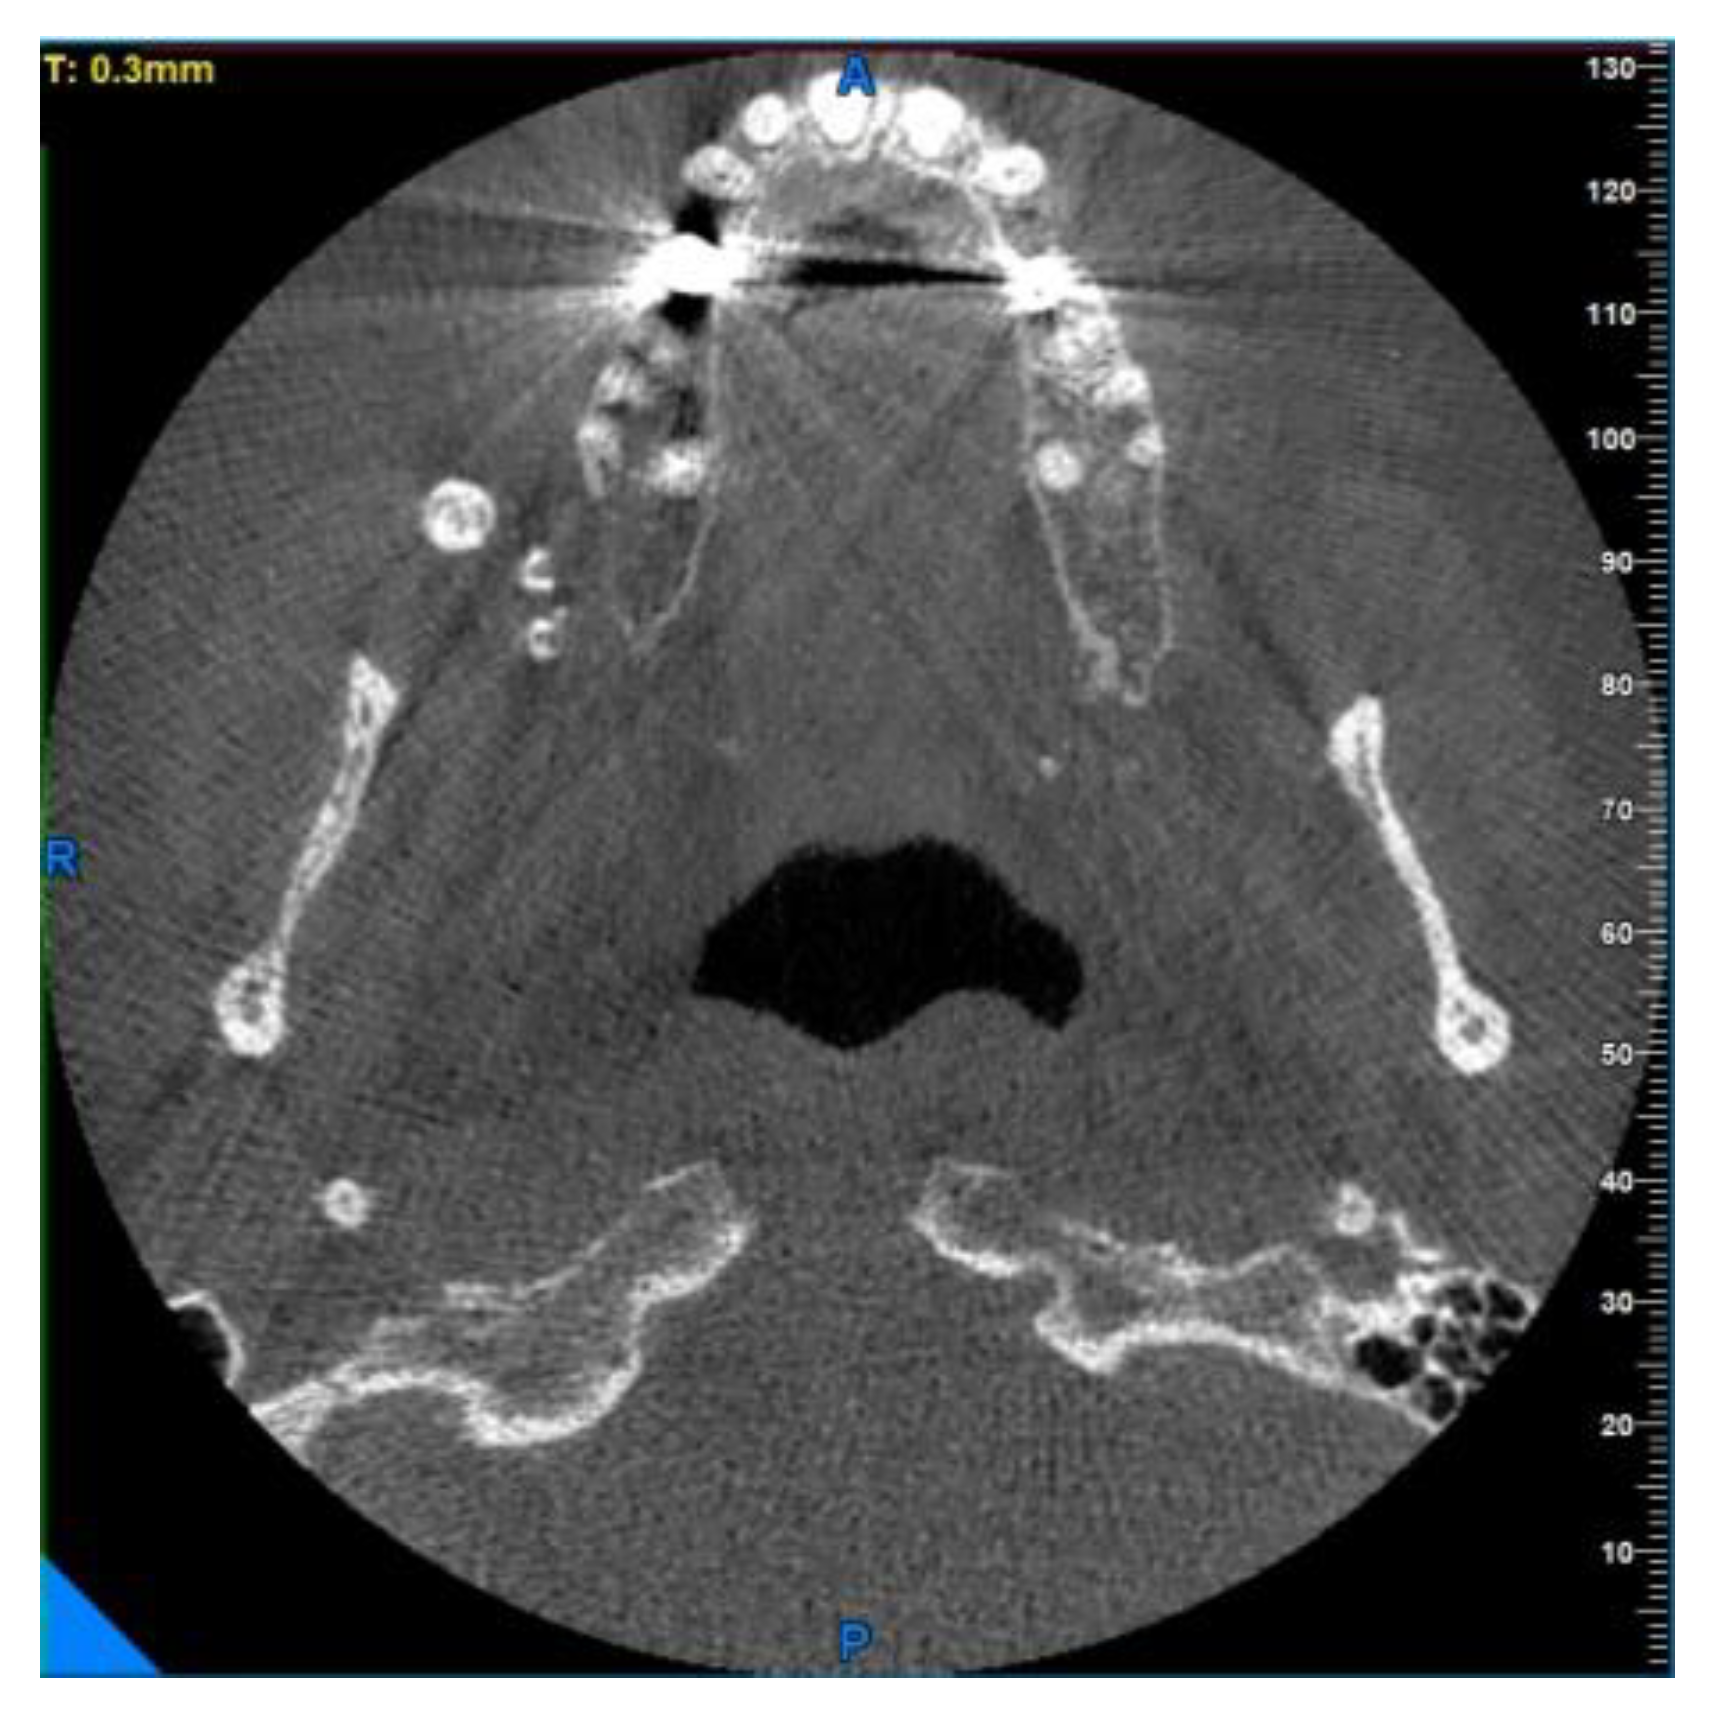

Enigmatic Formations Found in Routine Orthopantomography (OPG) Examinations: A Case Report

2. Case Presentation